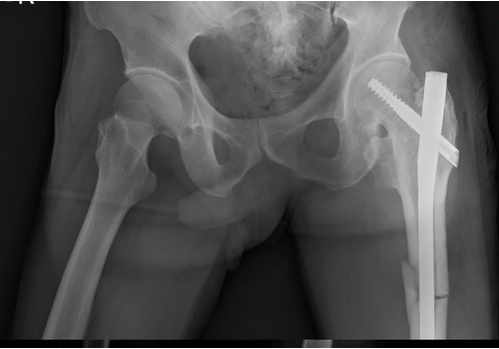

左圖:邱伯伯左側股骨骨折(大腿骨折),經過花蓮慈濟醫院麻醉團隊進行術前神經阻斷術、以及骨科團隊骨折固定手術(右圖)後,邱伯伯手術沒有了疼痛問題。